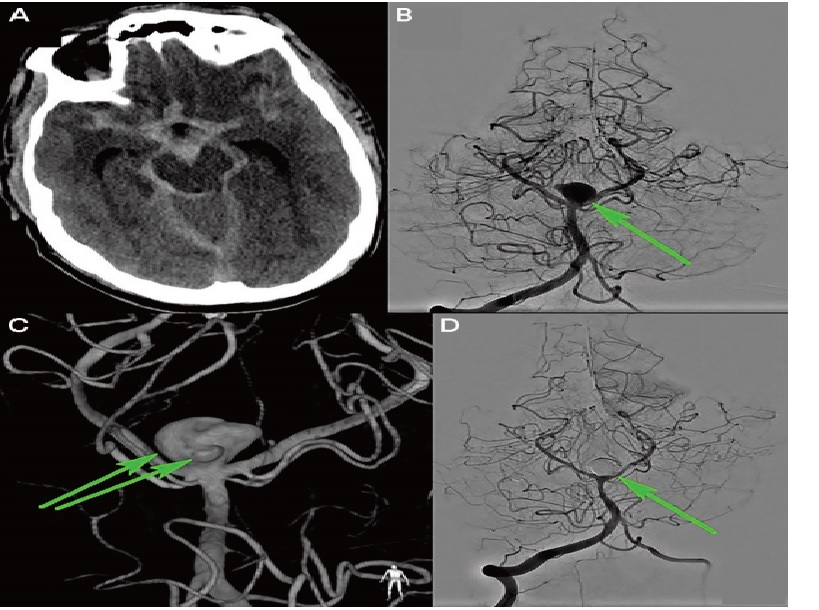

A noncontrast head CT revealed subarachnoid hemorrhage (SAH) in multiple cisterns, intraventricular hemorrhage, and mild hydrocephalus

Neuroimaging of the patient in CASE 1. Noncontrast head CT (A) showing acute subarachnoid hemorrhage, and two-dimensional (B) and three-dimensional (C) four-vessel angiogram showing a large top of the basilar artery aneurysm with an irregular shape (B, C, arrows). Two-dimensional angiogram after coiling shows obliteration of the aneurysm (D, arrow)

Nhận xét: Trường hợp này xử trí SAH giai đoạn đầu: chẩn đoán nhanh chóng SAH, hydrocephalus và điều trị cấp cứu ngay lập tức với hạ huyết áp, đặt EVD, và xóa bỏ túi phình động mạch não bị vỡ.